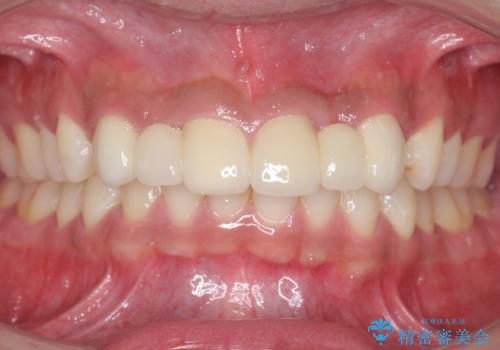

バラバラに位置している前歯の位置を矯正治療で修正してからブリッジを装着しています。

- 前歯ブリッジ85.8万円 (ジルコニアクラウン 12.1万円×6本 仮歯 1.1万円×6本)矯正費用別途費用は治療当時の料金となります

矯正治療によって事前に歯の位置を修正しているため、ダミーの歯の大きさも調整し、自然な仕上がりにしました。また、犬歯のねじれを治してから削っているため、神経をとらずに歯の形を整えることができました。